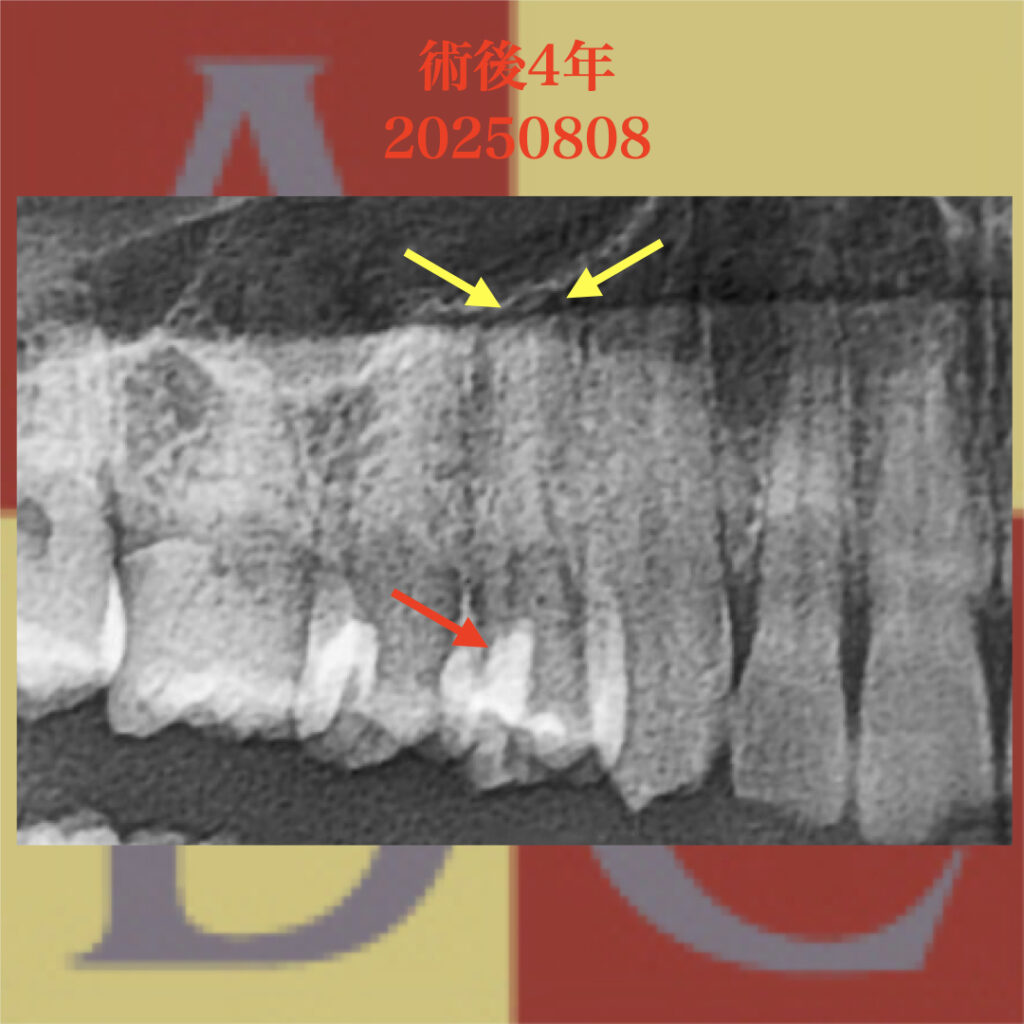

術後4年経過のパノラマX線写真

黄色の矢印の部分に歯根膜腔の連続性が確認できる

術前に見られた歯根膜の連続性が、術後も確認できる。

隣接する歯の歯髄よりも深い部分にまでMTAセメントが確認できる

メインテナンスにて経過を確認することが重要です!